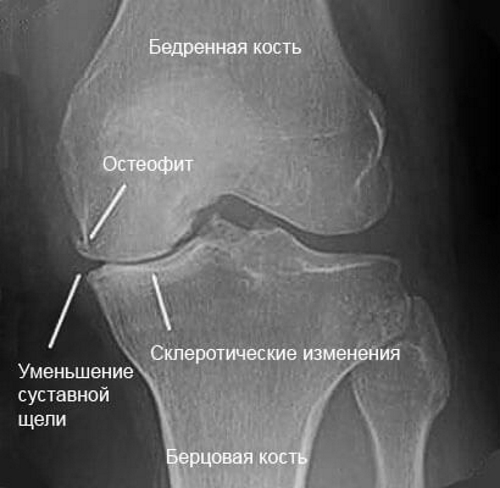

Вопрос о том, как справиться с проблемами коленей, должен решаться врачом после необходимых обследований, которые могут включать:

- рентгенографию;

- магнитно-резонансную томографию (МРТ);

- ультразвуковое исследование (УЗИ);

- компьютерную томографию.